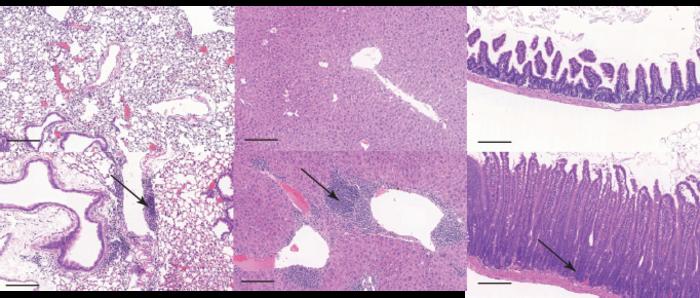

Representative images of sections (from L-R) of the lung, liver, and small intestine from control (upper panel) and knockout mice (lower panel) which displayed clinical signs. The arrows indicate accumulation of immune cells into these tissues. Tissue sections were stained with haematoxylin and eosin. Scale bar represents 200mm.